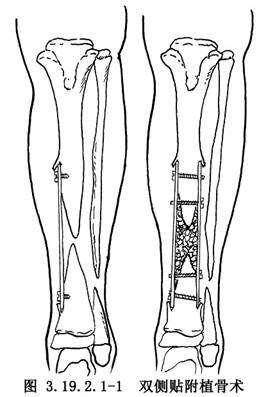

雙側貼附植骨術用於先天性脛骨假關節的手術治療。雙側貼附植骨術爲Boyd所創用。他認爲雙側皮質骨固定比較結實,對線好,可保持脛骨乾的足夠寬度,還可防止瘢痕壓迫植入的松質骨。如果一側植骨塊被吸收,其對側植骨塊仍存在,再骨折的可能性少,治癒率較高(圖3.19.2.1-1)。但該法對較低位脛骨假關節的遠端植骨片固定有一定難度。Tachdjian改良了Boyd手術,除雙側貼附植骨外,改用加壓器固定或斯氏針髓內固定,此法除解決了較低位脛骨假關節的固定問題,尚可促進骨癒合。手術相關解剖見下圖(圖3.19.2.1-2,3.19.2.1-3)。